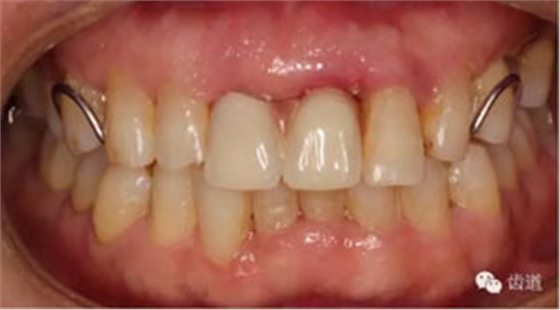

臨床檢查:11,21伸長(zhǎng)1-2mm,松動(dòng)1度,叩(+),21齦緣稍紅腫,唇側(cè)牙槽骨較豐滿,前牙咬合早接觸,中低位笑線,口腔衛(wèi)生一般。

初診照片(正面照)